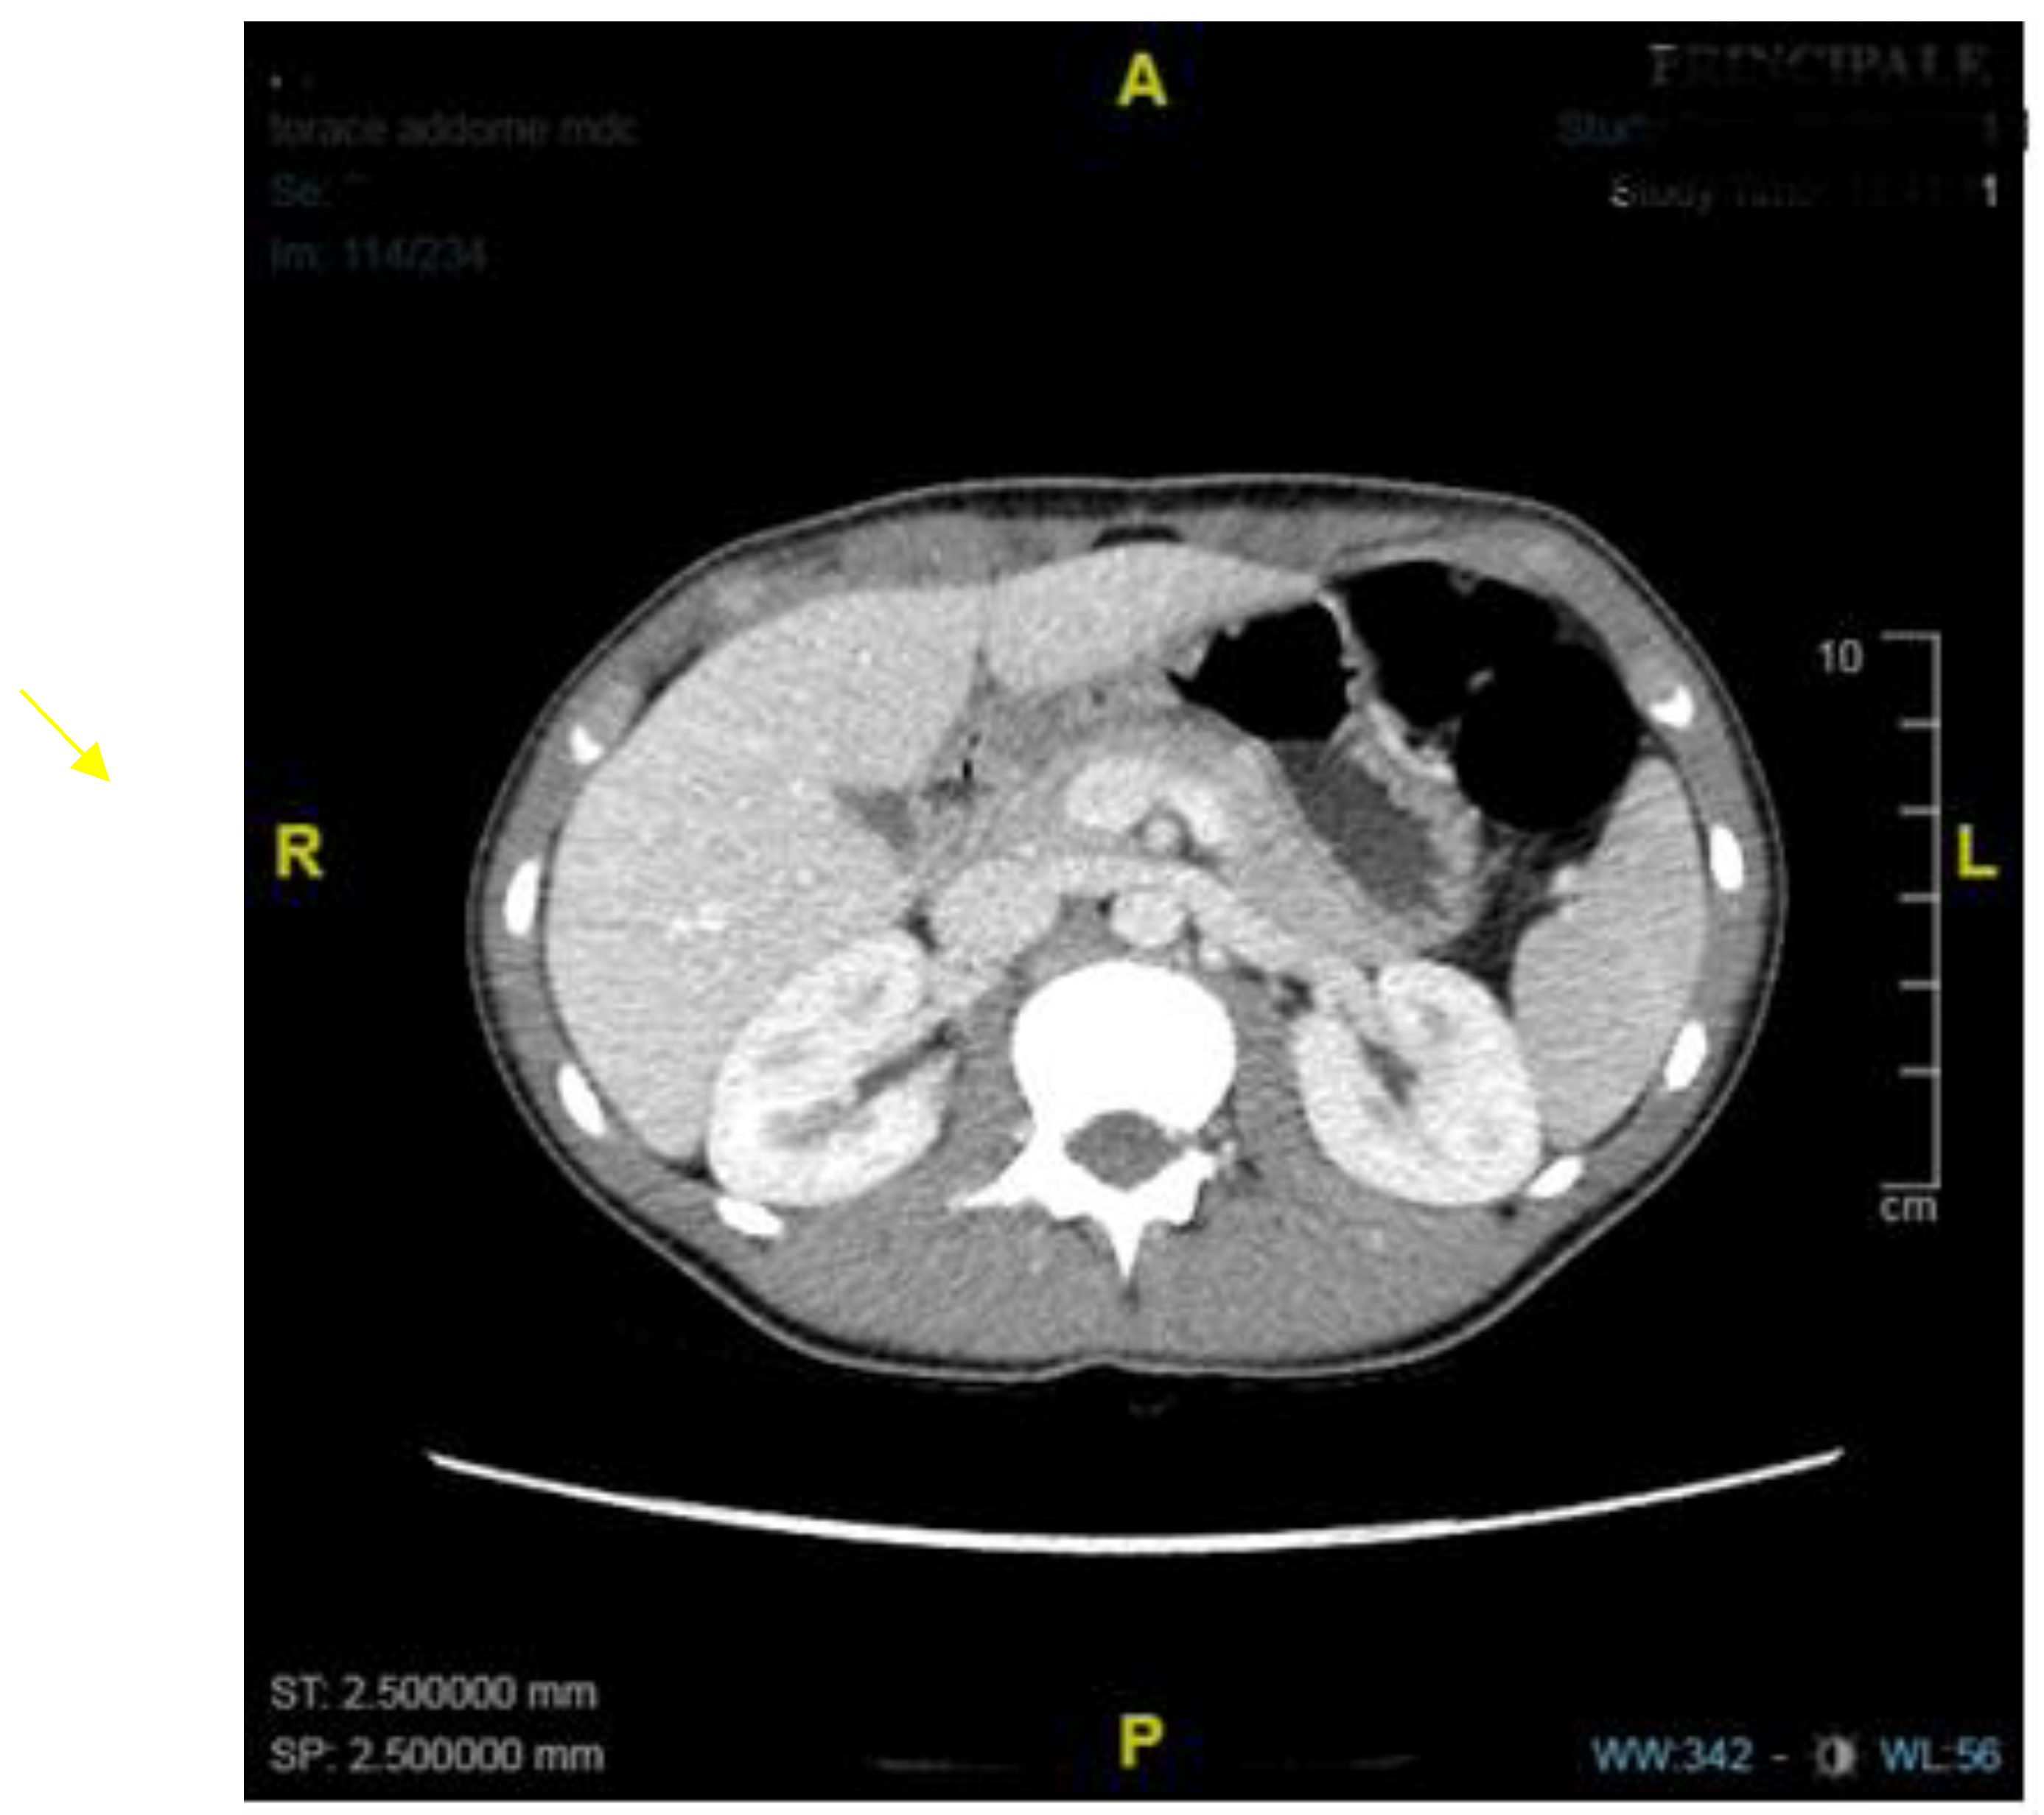

| Mahalik et al. [15], 2010 | 1 | 4,5 years | Non bilious vomiting | US, UGI series, CT scan | - | OP |

| Bajpai et al. [17], 2013 | 1 | 8 years | Non bilious vomiting and poor growth | US and X-Ray, EGDS, CT scan, UGI series | - | HMP + temporary jejunostomy |

| Oswari et al. [20], 2020 | 1 | 11 years | Vomiting, previous history of epigastric trauma | UGI series, EGDS, CT scan | B-I | |

| Iacoviello et al. [21], 2022 | 1 | 3 years | Vomiting, rumination and weight loss | Abdominal US and X-Ray, UGI series (2), CT scan, EGDS, MRI. | - | EBD (failure) OP |